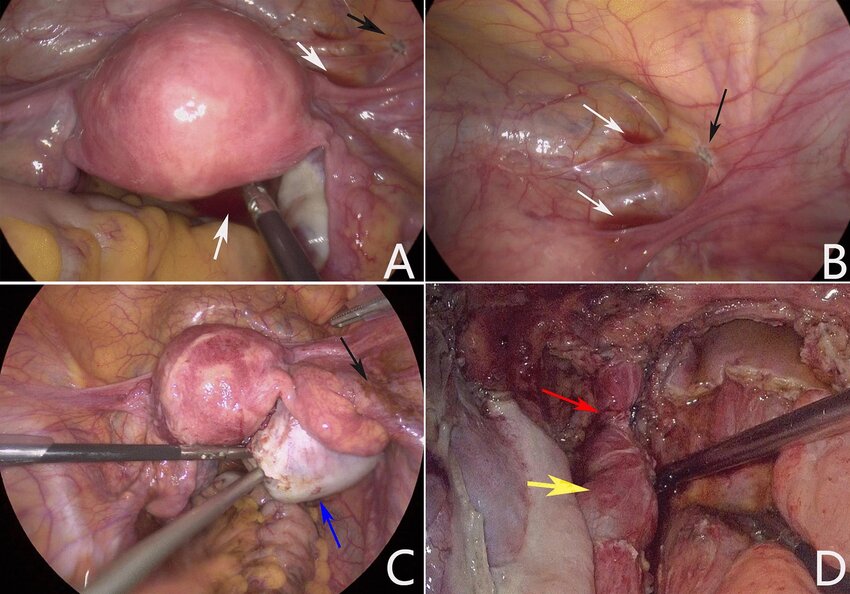

اندومتریوز معمولا با لاپاراسکوپی تایید می شود. این یک عمل کوچک است که شامل ایجاد یک برش کوچک، تحت بیهوشی، در دیواره شکم (شکم) زیر دکمه شکم (ناف) است. یک ابزار نازک تلسکوپ مانند (لاپاروسکوپ) از طریق پوست فشار داده می شود تا به داخل آن نگاه کند. تکه های اندومتریوز توسط پزشک قابل مشاهده است.با این حال، علائم آندومتریوز می تواند ناشی از شرایط دیگر باشد. بنابراین، اگر هر یک از علائم آندومتریوز بالا ماندگار شد، معمولاً آزمایشاتی برای یافتن علت علائم توصیه می شود.

لاپاراسکوپی

این روش جراحی با بیهوشی عمومی انجام میشود. پزشک از طریق یک برش کوچک در شکم دوربین کوچکی را وارد میکند تا به طور مستقیم داخل لگن را مشاهده کرده و در صورت نیاز نمونهبرداری (بیوپسی) انجام دهد. لاپاراسکوپی دقیقترین روش برای تشخیص قطعی اندومتریوز است و به پزشک این امکان را میدهد که ضایعات اندومتریوز را شناسایی و درمان کند.

در برخی موارد، پزشک متخصص برای بررسی دقیقتر، بیمار را برای انجام عمل لاپاراسکوپی به جراح ارجاع میدهد. لاپاراسکوپی نوعی جراحی کمتهاجمی است که با بیهوشی عمومی انجام میشود. طی این روش، برشی کوچک در نزدیکی ناف ایجاد شده و ابزاری باریک و بلند با دوربین کوچکی به نام لاپاراسکوپ وارد حفره شکمی میشود. پزشک از طریق این دوربین میتواند داخل شکم را مشاهده کرده و نشانههای وجود بافتهای اندومتریوز را بررسی کند. همچنین امکان برداشت نمونههای بافتی برای آزمایشهای بیشتر فراهم میشود. اطلاعاتی مانند محل دقیق، میزان گسترش و اندازه ضایعات با این روش بهدست میآید.

جراحی برای اندومتریوز

گاهی اوقات جراحی برای برداشتن برخی از تکه های بزرگتر اندومتریوز توصیه می شود. اگر مشکل ناباروری باشد، عمل ممکن است علائم را کاهش دهد و احتمال بارداری را افزایش دهد.تکنیک های مختلفی وجود دارد که می توان از آنها استفاده کرد. معمولاً یک ابزار نازک تلسکوپ مانند (لاپاروسکوپ) از طریق یک بریدگی کوچک در شکم (شکم) رانده می شود. سپس جراح از لاپاراسکوپ برای دیدن داخل شکم و برداشتن کیست ها یا سایر بافت های اندومتریوز (جراحی سوراخ کلید) استفاده می کند.

لاپاراسکوپی برای تشخیص و درمان آندومتریوزلاپاراسکوپی تحت بیهوشی عمومی انجام می شود. ممکن است یکی برای تایید تشخیص آندومتریوز داشته باشید. متخصص شما همچنین ممکن است در همان زمان رضایت شما را برای درمان هر تکه بزرگی که ممکن است پیدا کند (همانطور که قبلا توضیح داده شد) "در حالی که آنها در آنجا هستند" درخواست کند. این باعث صرفه جویی در انجام دو لاپاراسکوپی - یکی برای تشخیص و دیگری برای درمان می شود.

نحوه تشخیص آندومتریوز

بسیاری از افراد مبتلا به اندومتریوز بر اساس علائم خود بدون تشخیص رسمی درمان می شوند. در موارد دیگر، تشخیص رسمی از طریق لاپاراسکوپی، یک جراحی ساده انجام می شود. در این روش، پزشکان یک برش کوچک در شکم ایجاد میکنند (معمولاً زیر 1.5 سانتیمتر/0.6 اینچ) و دوربینی را برای مشاهده داخل حفره لگن وارد میکنند. نمونههای بافت کوچک ممکن است جمعآوری شوند که بیوپسی نامیده میشوند.

عمل جراحي

در برخی موارد، پزشک ممکن است لاپاراسکوپی را برای کاوش و برداشتن یا تخریب بافت مشکلدار با جراحی پیشنهاد کند. این می تواند به علائم کمک کند و باروری را بهبود بخشد .پزشکان ممکن است برداشتن لاپاراسکوپی یا ابلیشن را انجام دهند. اکسیزیون شامل بریدن بافت مشکل ساز است، در حالی که فرسایش شامل سوزاندن بافت از طریق کوتریزاسیون یا لیزر است.

پزشک تاریخچه پزشکی بیمار را دریافت می کند و معاینه دقیقی از جمله معاینه لگنی برای شناسایی هرگونه ناهنجاری قابل لمس انجام می دهد. تصویربرداری، مانند سونوگرافی ترانس واژینال و تصویربرداری تشدید مغناطیسی، ممکن است انجام شود. لاپاراسکوپی، نوعی جراحی کم تهاجمی، تنها راه برای تایید اندومتریوز است. بیوپسی و ارزیابی میکروسکوپی ضایعات احتمالی اندومتریوز می تواند اندومتریوز را تایید کند.

لاپاراسکوپی

بیشتر آندومتریوز باید با دیدن آن به طور دقیق و مستقیم تشخیص داده شود. این بدان معناست که بیماران باید حداقل یک نوع جراحی جزئی به نام لاپاراسکوپی انجام دهند.

در این عمل یک برش کوچک در ناف ایجاد می شود و سپس یک تلسکوپ به داخل حفره شکم وارد می شود تا تمام اندام ها و سطوح لگن را به دقت بررسی کند. به این ترتیب می توان اندومتریوز را به درستی شناسایی کرد و شدت آن را ارزیابی کرد.

لاپاراسکوپی

این یک روش جراحی برای درمان آندومتریوز است که در آن جراح با استفاده از یک گاز بی ضرر، شکم را کمی باد می کند و یک ابزار بینایی کوچک را به داخل شکم وارد می کند که به آن لاپاراسکوپ می گویند. سپس جراح حداقل دو برش کوچک دیگر در شکم ایجاد می کند و لیزر را برای برداشتن ضایعات از طریق فرآیندی به نام بریدن وارد می کند. ضایعات با استفاده از گرمای شدید از بین می روند و رگ های خونی بدون بخیه بسته می شوند، با فرآیندی به نام کوتریزاسیون. گاهی اوقات جراحان بافتهای اسکار را نیز برمیدارند زیرا ممکن است بر درد آندومتریوز بیفزایند.